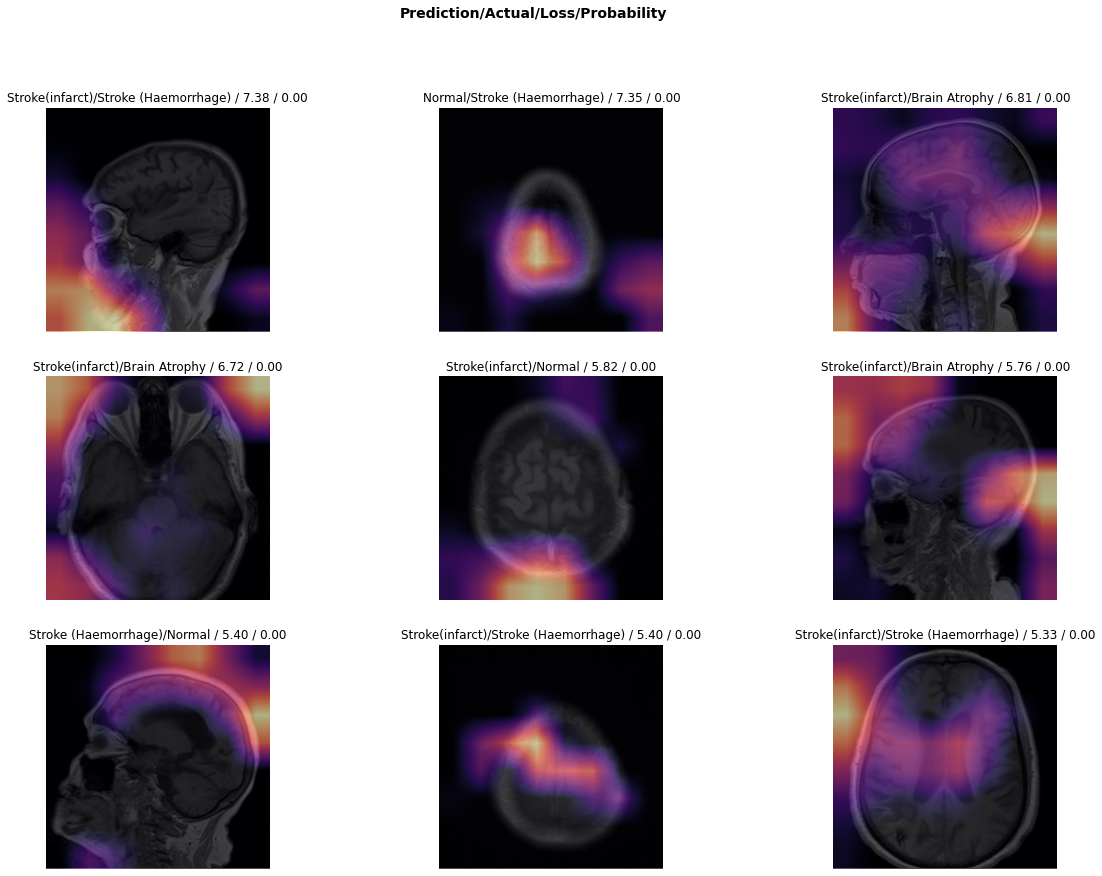

5.1 Experiment I: National Institute of Neuroscience and Hospitals dataset

5.1.1 Stage I: Retraining the Network

In the first stage, we re-trained the model as a benchmark by freezing the convolution base layers of the network and did not update its weights during this stage. The weight updates only occurred in the fully-connected layers of the network. We utilized the multinomial logistic cost function to measure the loss and a step size of 0.010960.010960.01096. We set the number of epochs to 8 to ensure the model does not overfit on the training set because small, and highly imbalanced dataset tends towards model overfitting, which affects out-of-sample performance. On completing the first stage of the training, the model showed an overall accuracy of 87.43% using a fivefold cross-validation strategy. Fig 6 shows the top miss-classified images during this phase of training.

Refer to caption

Figure 6: Illustration of top miss-classified images after stage I of training